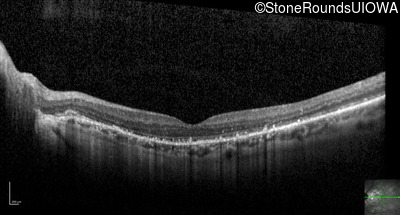

Optical Coherence Tomography - Right - 20/25 +1

Exemplar / OCT Stack

OCT Stack